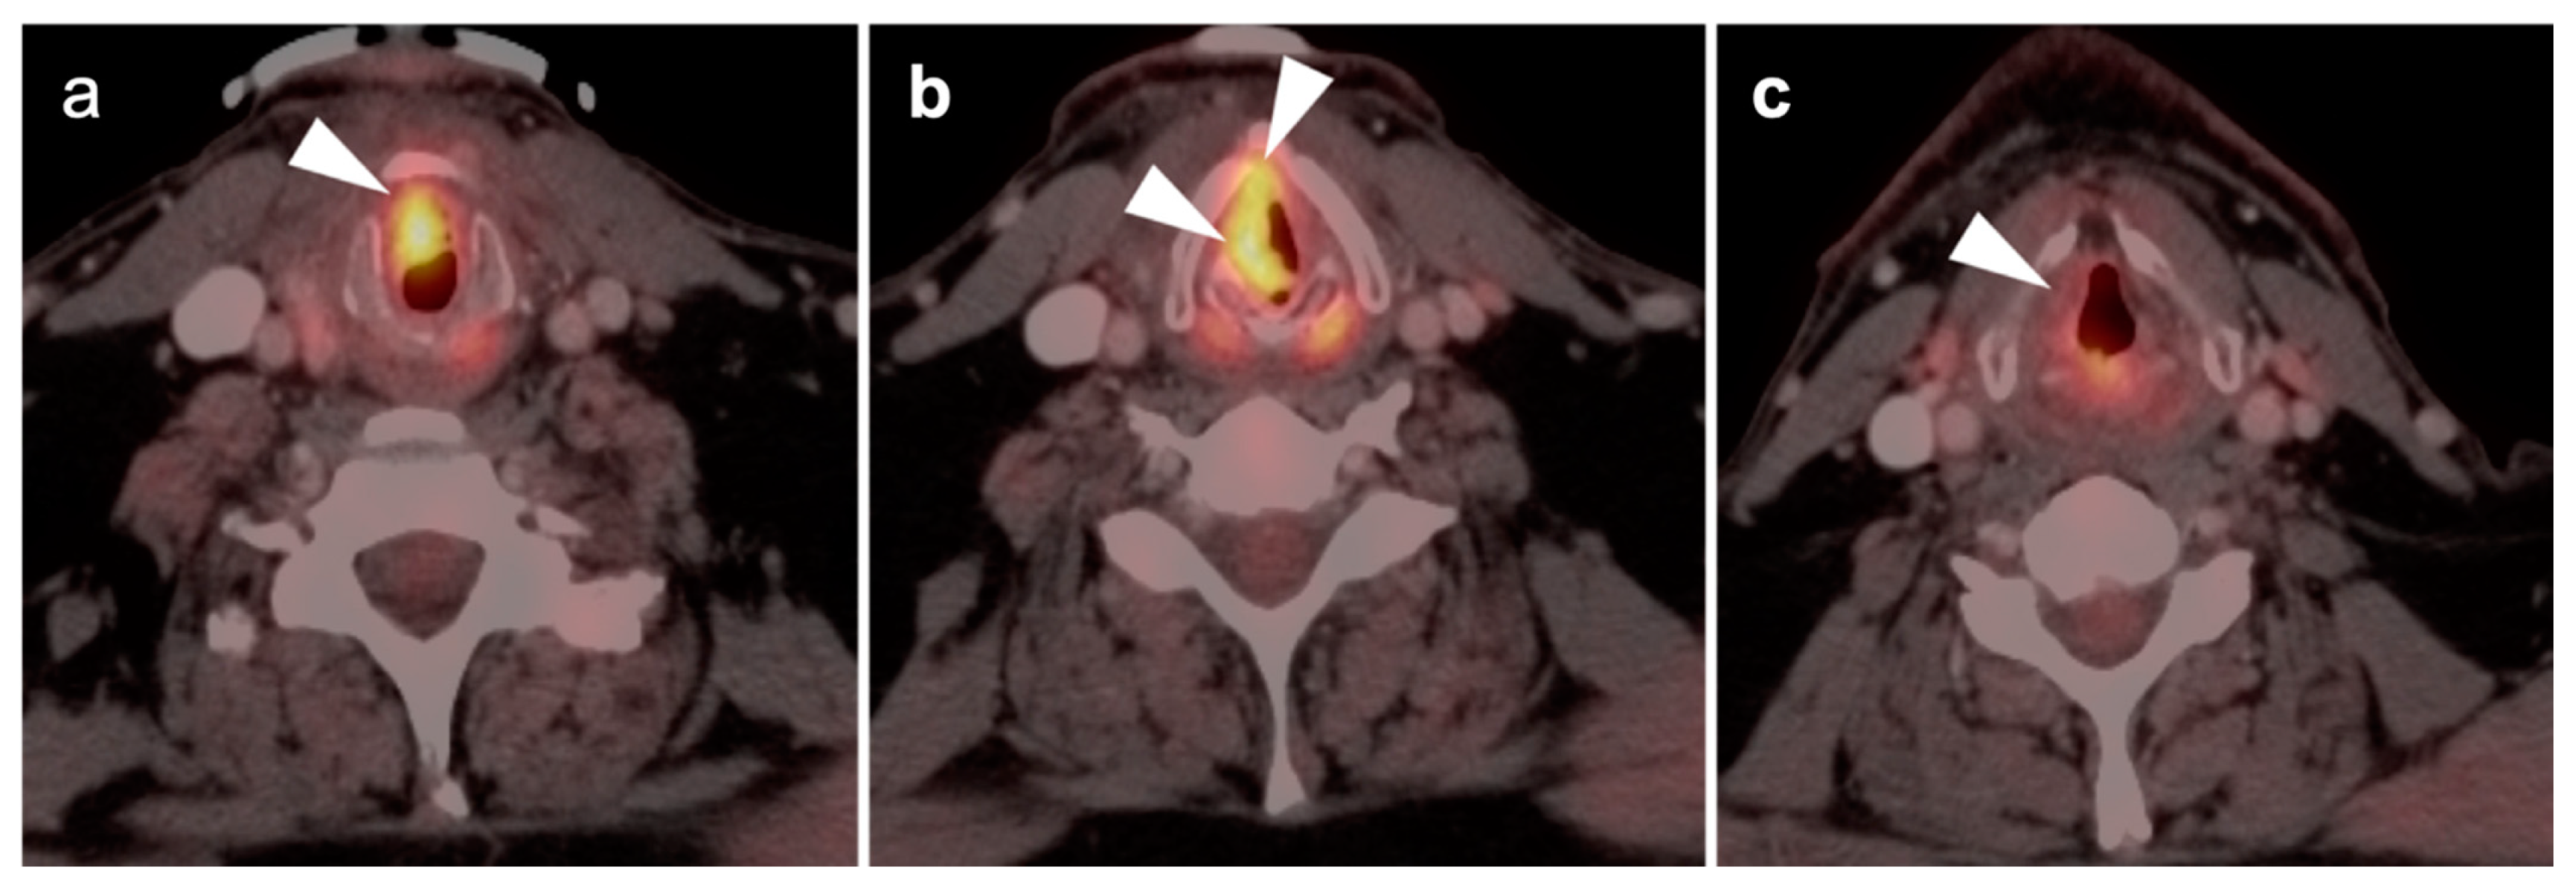

- Laryngeal squamous cell carcinoma

- a.

- Supraglottic larynx

- b.

- Glottic larynx

- c.

- Subglottic larynx